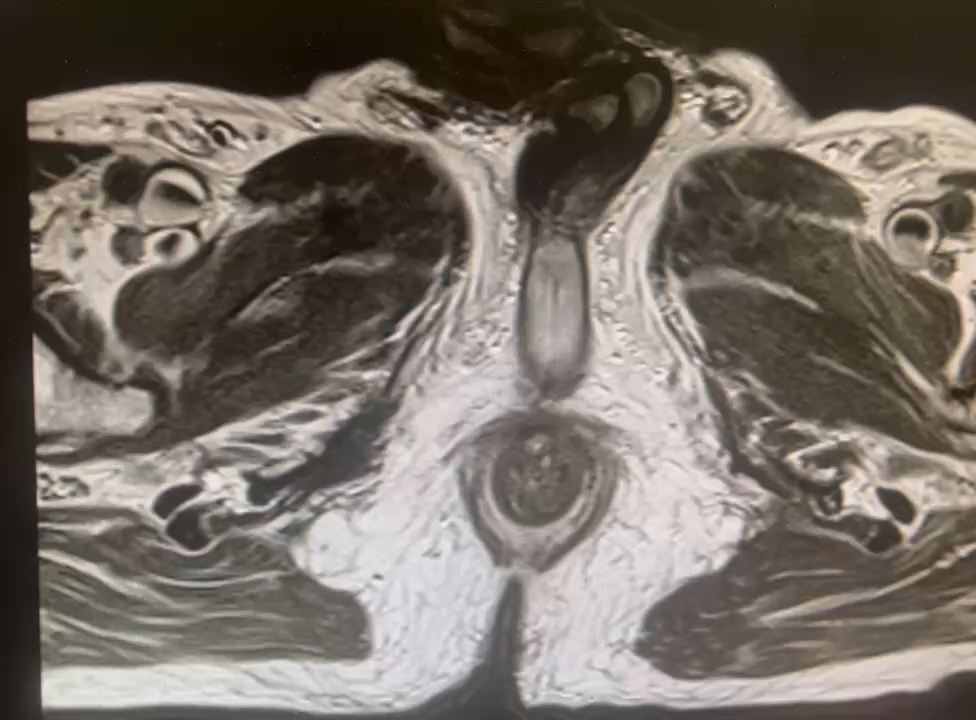

李建兴教授团队还进行了复杂性肾、输尿管结石,肾脏铸型结石碎石取石术、经皮肾镜碎石术、感染性结石EMS碎石取石术,输尿管软镜碎石术以及可视穿刺超细通道(Needle-perc)经皮肾镜碎石术,前列腺癌腹腔镜下前列腺癌根治性切除术、前列腺增生经尿道膀胱前列腺激光剜除术等手术演示。